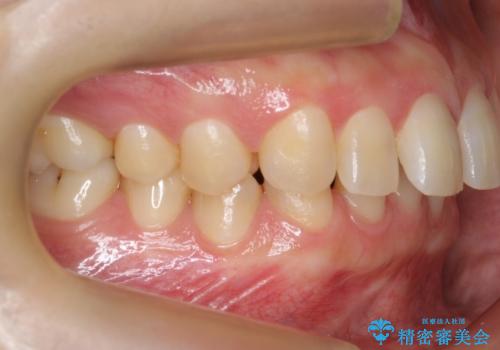

奥歯が1歯対1歯で、過蓋咬合を呈していました。

レントゲンで、右上4番の近心の垂直的骨欠損があり、抜歯を行うこととしました。

右上4の垂直性骨欠損については再生療法を行う選択肢もありました。

しかし、過蓋咬合であり、咬頭対咬頭の咬合では根本的な解決は見込めないことから、矯正治療を希望されていたこともあり、相談の上抜歯しました。

すぐに欠損するわけではないですが、最初の噛み合わせのまま4番が欠損をしたことを考えると、ブリッジやインプラントでも咬合により負担は大きくなってしまうことが考えられます。